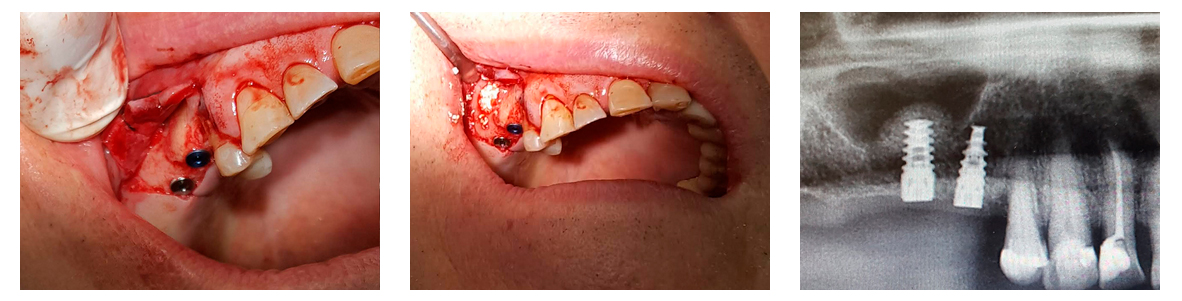

Sinus lifting was performed simultaneously with implantation. (Syntoss Bone Graft, DSI Premium Implants, DSI Silk 5.0 sutures). After a four-month recovery period, trepan open implants and abutments added using a direct impression technique.